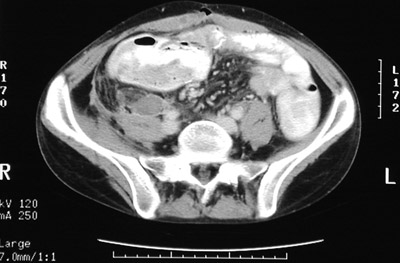

| Here are two views of an abdominal CT scan which reveal inflammatory changes in the right lower quadrant in the region of the cecum that resulted from neutropenic colitis. This immunocompromised state, which can occur with leukemia, chemotherapy, and other conditions that reduce the number of neutrophils, predisposes to inflammation, particularly in the region of the cecum. |